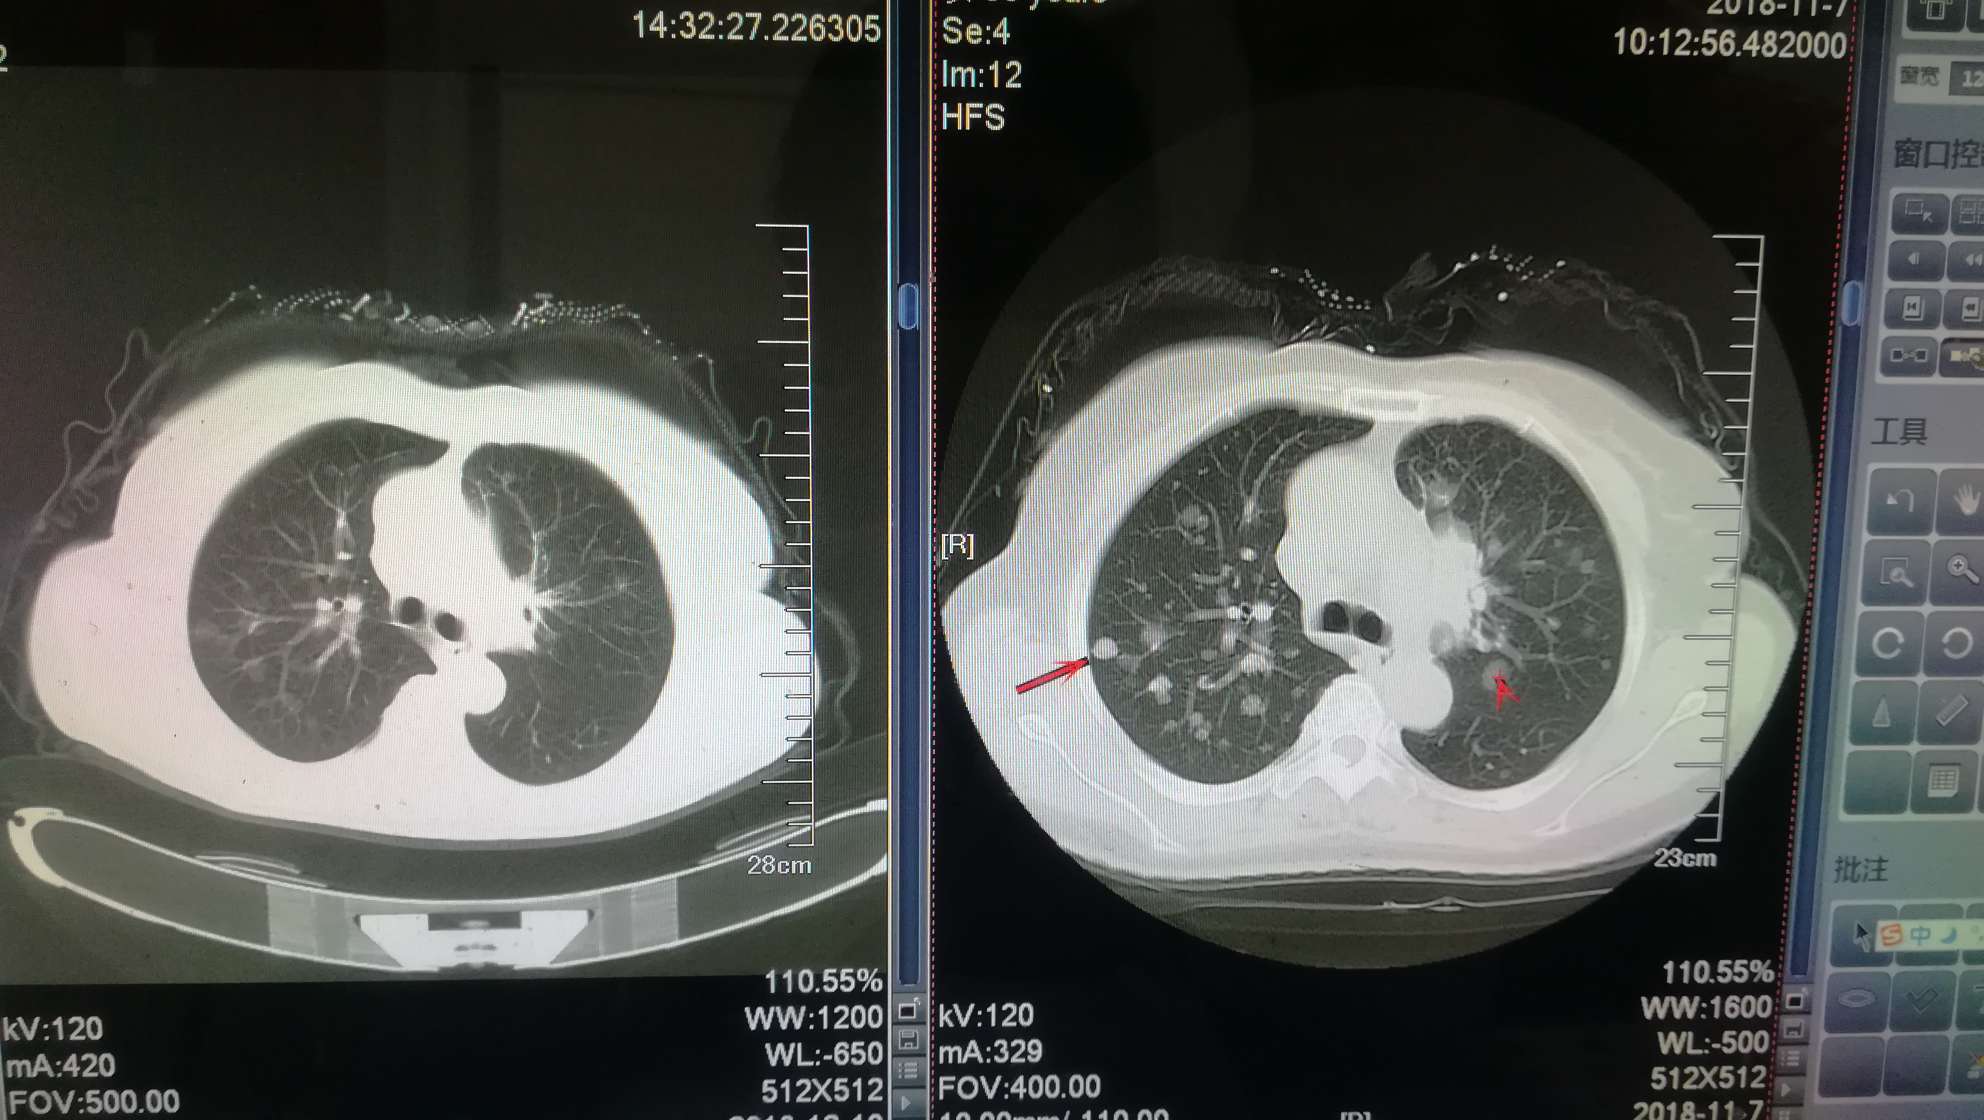

11月复查病灶有增大,医生判断易瑞沙缓慢耐药,血检无T790突变,因第一次我妈做穿刺遭了不少罪,所以暂时没重新穿刺。

刚刚带我妈复查回来,特罗凯联184 初见成效 肺内结节有缩小,现在心里还有点小激动。希望妈妈越来越好,觅友们越来越好。